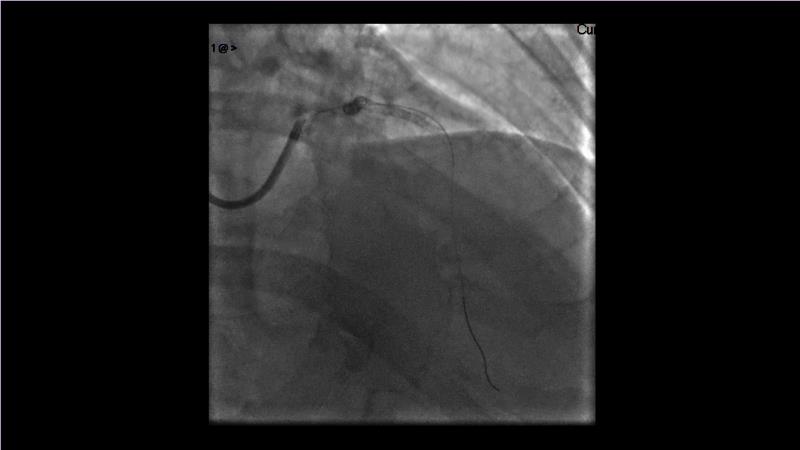

Browse this EuroPCR 2024 session to explore the safety and efficacy of sirolimus-coated balloons from pre-clinical data, review MagicTouch data from real-world populations with case-based examples, and learn about the MagicTouch sirolimus-coated balloon clinical programs. Discover insights and takeaways from the significance of the EASTBOURNE subgroups, and analyze the challenges and opportunities in PCI for diabetic patients.